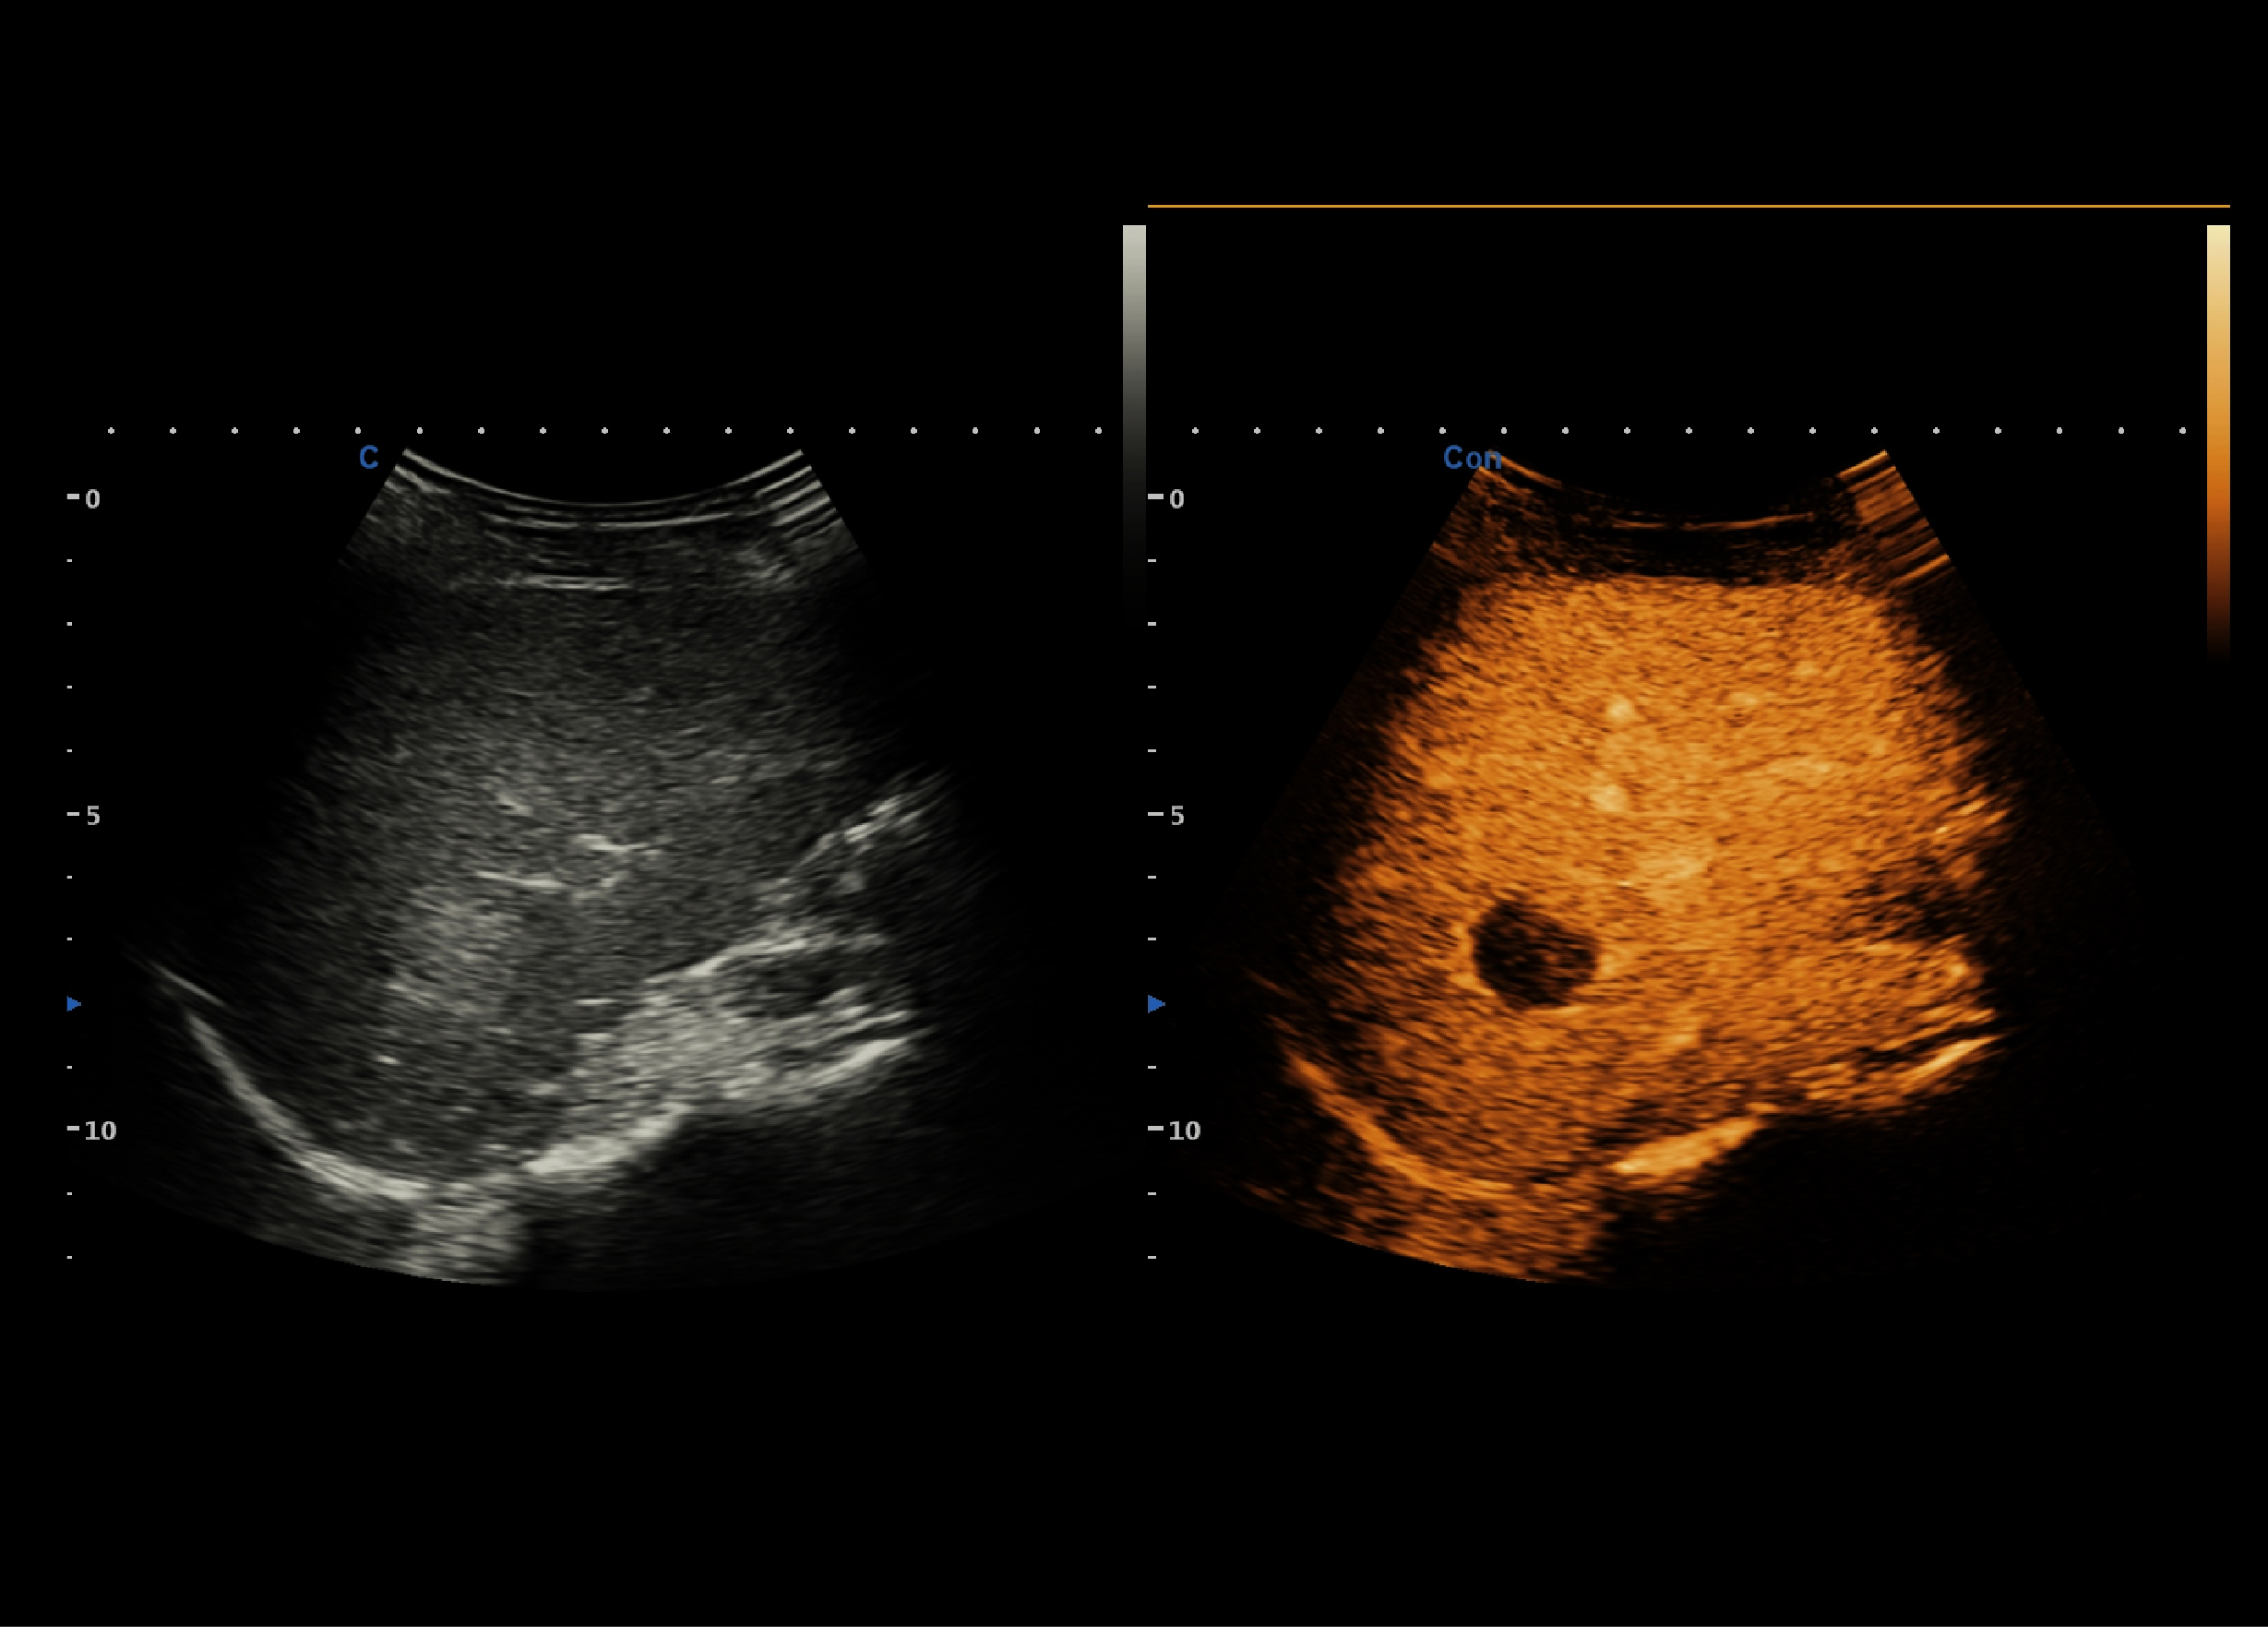

通过外周静脉注射超声造影剂,清楚显示微细血管和组织血流灌注,观察待查目标与周围组织的造影灌注特征(即增强特征)的差别,以此提高病变的检出率以及诊断的准确性。